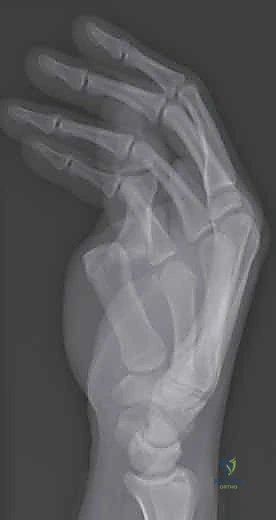

2. التصوير بالأشعة السينية (X-rays)

يُعد التصوير الشعاعي الخطوة الأولى لاستبعاد وجود كسور مصاحبة. في كثير من الأحيان، ينسلخ الرباط ويسحب معه قطعة صغيرة من العظم (Avulsion fracture). كما يتم أخذ صور أشعة تحت الإجهاد (Stress X-rays) لتوثيق عدم الاستقرار.